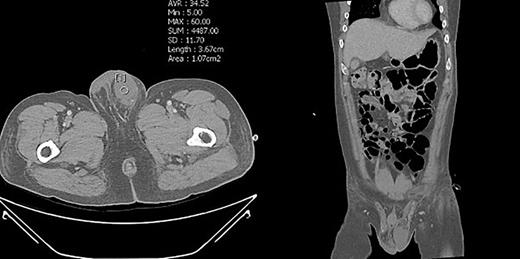

Enhanced abdominal pelvis CT of the patient. The left testis of the left scrotum revealed patent with showing vascularity.

To prevent the patient from further self-injury, simple therapeutic restraint of both arms was performed with the patient’s consent, and sedative medication was administered. He was closely observed in the intensive care unit to monitor his hemoglobin and systemic conditions. Additional transfusion treatment was provided as needed. Psychiatric medicines including antipsychotics and sedatives (Clozapine 125–250 mg/day, haloperidol 2.5–5 mg, and lorazepam 1–2 mg/day) were prescribed by a psychiatrist. After 5 days of taking the psychiatric medication, the patient no longer reported the impulse to harm himself, and was able to release the simple restraint on both arms. No further self-harm occurred until he was discharged, presumably due to the proper effects of taking psychiatric medication. Anticoagulant agents (5 mg apixaban, twice per day), subcutaneous heparin injection (5,000 IU, twice per day), and alprostadil (10 mg, once per day) were given for circulation to prevent the thrombosis of vessels. On POD2 from the first operation, a testicular scan with technetium pertechnetate revealed the viability of the remnant left testis compared with the amputated right testis (Fig. 7). On POD4, contrast-enhanced CT showed the enhancement of the vessel into the testis (Fig. 8). On POD7, scrotum Doppler ultrasonography revealed the Doppler signal in the parenchyma of the testis (Fig. 9). Testosterone levels increased after the surgeries and normalized on POD5 (Fig. 10). He was discharged on POD9 without any skin complication (Fig. 6c). After discharge, he returned to our clinic for follow-up on POD13 and 23. On the visit, laboratory follow-up including testosterone and free testosterone was checked and confirmed as normal (Fig. 10).

We performed five examinations to check the viability of the replanted testis. First, in the operating room, we used indocyanine green after replantation (Fig. 4). Indocyanine green fluorescence perfusion showed testicular perfusion, which enabled the immediate checking of the viability of vessels. This procedure is appropriate for checking the viability of microscopic vessels that may be damaged during a milking test. Second, a testicular scan showed the viability of the testis (Fig. 7). One testis is markedly different from the lesion of orchiectomy. However, the scan resolution was low because of a wide range of arterial courses and the disturbance of the urethral catheter or bladder. Third, contrast-enhanced CT displayed the vascularity of the testis and the surrounding parts (Fig. 8). However, the shooting time to the enhanced phase could affect the failure of the vascularity of the testis. No protocol for this case has been established in our institute; therefore, CT was a nonspecific tool for testicular examination. Fourth, ultrasonography efficiently showed the vascularity inside the testis (Fig. 9). However, skin wound could inhibit or limit ultrasonography. Fifth, we indirectly checked the testicular function based on testosterone levels (Fig. 10). A laboratory examination should be performed continuously. However, this procedure could be limited among hypogonadal men, and the separate testicular function of each testis could not be easily identified. Nevertheless, these techniques will help determine the viability of the testis in specific situations.